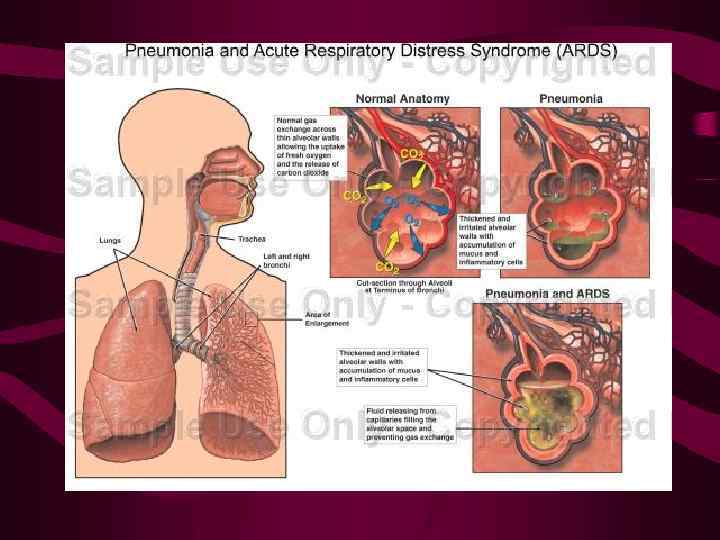

Отеки при повреждении капилляров Синдром острого повреждения легких (СОПЛ), респираторный дистресс синдромом взрослых (РДСВ), синдром шокового легкого (СШК), синдром влажных легких, некардиогенный отек легких и т. д.

Отеки при повреждении капилляров Синдром острого повреждения легких (СОПЛ), респираторный дистресс синдромом взрослых (РДСВ), синдром шокового легкого (СШК), синдром влажных легких, некардиогенный отек легких и т. д.

Отеки при повреждении капилляров Повреждение стенок легочных капилляров, прежде всего их базальной мембраны возникает при эндогенных и экзогенных воздействиях на микроциркуляторное русло.

Отеки при повреждении капилляров Повреждение стенок легочных капилляров, прежде всего их базальной мембраны возникает при эндогенных и экзогенных воздействиях на микроциркуляторное русло.

В результате повреждения стенок капилляров в экссудат с высоким содержание белков и форменных элементов крови. легочную ткань проникает В наиболее тяжелых случаях развивается геморрагический отек легких, представляющий собой кровоизлияние в легкие. Такой патогенетический вариант определяется как отек при повреждении капилляров. Он является важной составной частью самостоятельного патологического процесса - респираторного дистресс-синдрома взрослых (РДСВ).

В результате повреждения стенок капилляров в экссудат с высоким содержание белков и форменных элементов крови. легочную ткань проникает В наиболее тяжелых случаях развивается геморрагический отек легких, представляющий собой кровоизлияние в легкие. Такой патогенетический вариант определяется как отек при повреждении капилляров. Он является важной составной частью самостоятельного патологического процесса - респираторного дистресс-синдрома взрослых (РДСВ).